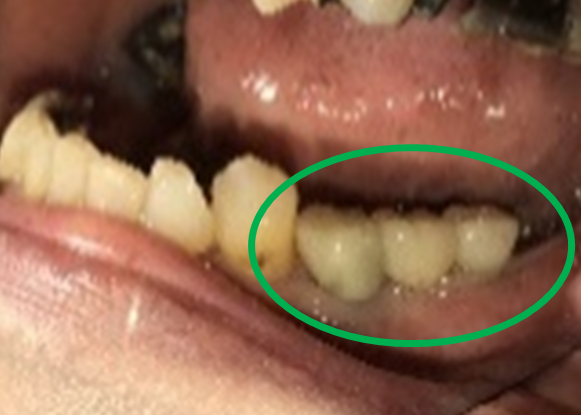

Before

※赤丸は、歯根が破折していたため抜歯しました

※黄色丸は、2006年10月に埋入したインプラント

After

※緑丸は、今回埋入したインプラント